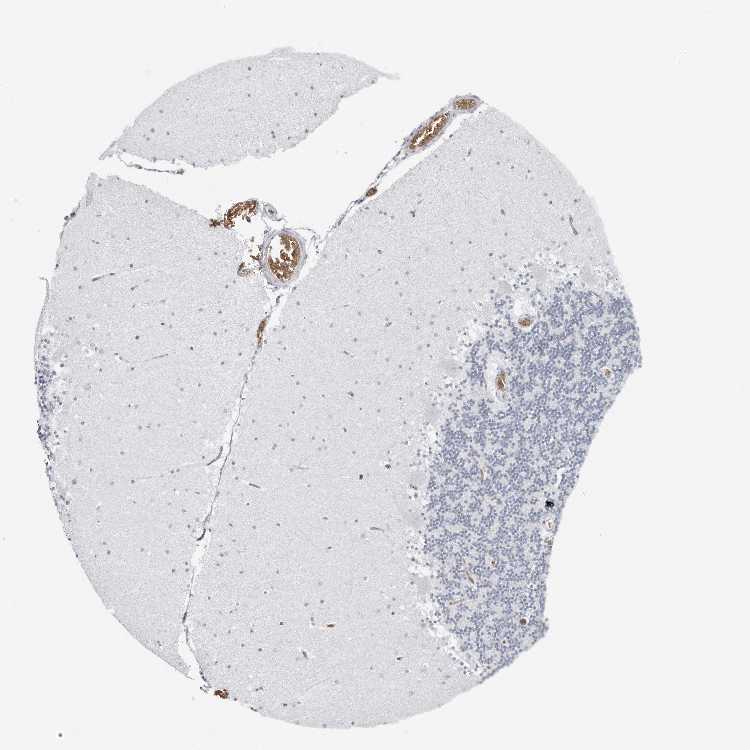

CEREBELLUM - Antibody stainingi

Antibody staining in the annotated cell types in the current human tissue is reported as not detected, low, medium, or high, based on conventional immunohistochemistry profiling in selected tissues. This score is based on the combination of the staining intensity and fraction of stained cells.

Each image is clickable and will lead to virtual microscopy that enables deeper exploration of all samples and also displays staining intensity scores, fraction scores and subcellular localization as well as patient and tissue information for each sample.

Antibody HPA028414

Purkinje cells Not detected

Cells in granular layer Not detected

Cells in molecular layer Not detected